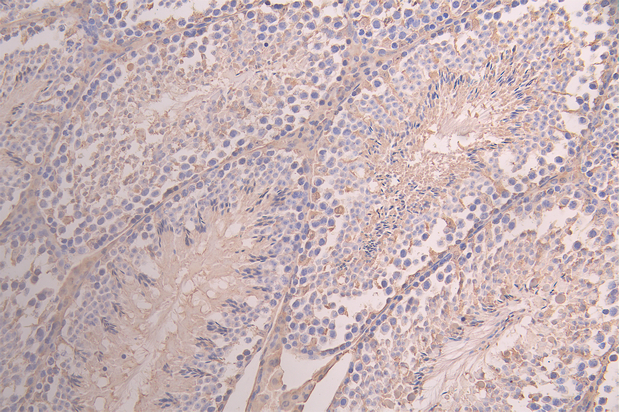

IHC image of CSB-RA732978MA1HU diluted at 1:100 and staining in paraffin-embedded human breast cancer performed on a Leica BondTM system. After dewaxing and hydration, antigen retrieval was mediated by high pressure in a citrate buffer (pH 6.0). Section was blocked with 10% normal goat serum 30min at RT. Then primary antibody (1% BSA) was incubated at 4°C overnight. The primary is detected by a Goat anti-human polymer IgG labeled by HRP and visualized using 0.05% DAB.